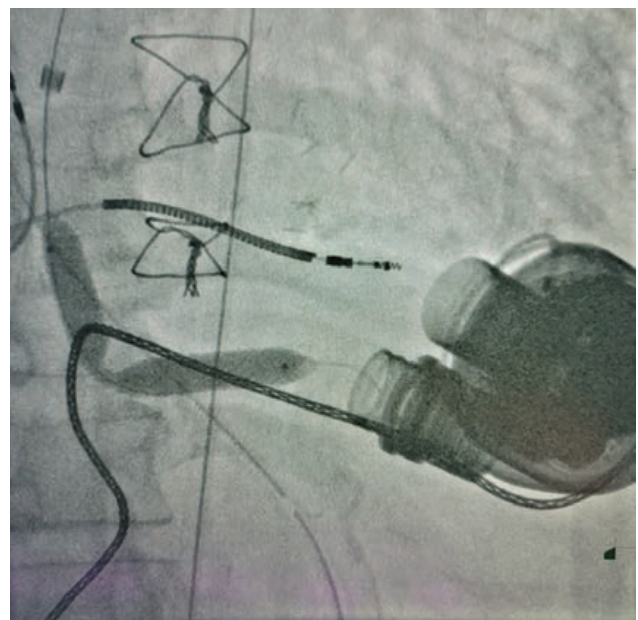

Initially, we attempted to snare the stent from both sides via two vascular accesses. To snare the upper portion of the stent, a 20 mm Amplatz Goose Neck snare (Medtronic) was introduced through a 23 cm 8 French (F) sheath in the right internal jugular vein. Simultaneously, a 30 mm Amplatz Goose Neck snare was introduced through a 30 cm 14F sheath in the right femoral vein to snare the bottom part of the stent. This method of stent retrieval was not successful; therefore, we had to rethink our strategy.

We upsized the 14F sheath to 24F and placed a second 20F sheath within it. We put a third 16F sheath inside these two previous 24F and 20F sheaths. Dr. Nelson Bernardo, an interventional cardiologist at Medstar Washington Hospital Center, practices this technique, known as mother-child-grandchild. The two snares described previously were used to capture both sides of the stent with the top snare pulling from the top and the bottom snare pulling from below, preventing the stent from embolizing into the right ventricle and slowly bringing it down into the inferior vena cava. The traction of the stent’s edge elongated it and made it smaller, which allowed us to capture its middle portion with a third 35 mm Amplatz Goose Neck snare. The stent was then pulled as a unit into the 16F sheath. Then the stent was pulled together with the 16F and 20F sheaths, taking them out of the 24F sheath as a single unit. A repeat fluoroscopy was performed to ensure that no residual pieces were left behind, and an angiogram was performed to confirm that there was no evidence of dissection. Upon examination, the stent was found to be intact and to have been endothelialized much earlier than expected. In the common femoral vein, hemostasis was achieved using a Perclose (Abbott). While in the internal jugular vein, hemostasis was achieved by manual compression.